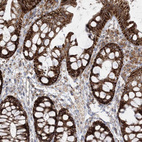

Immunohistochemical staining of human cerebellum, gastrointestinal, kidney and skeletal muscle using Anti-LRPPRC antibody HPA036408 (A) shows similar protein distribution across tissues to independent antibody HPA036409 (B).